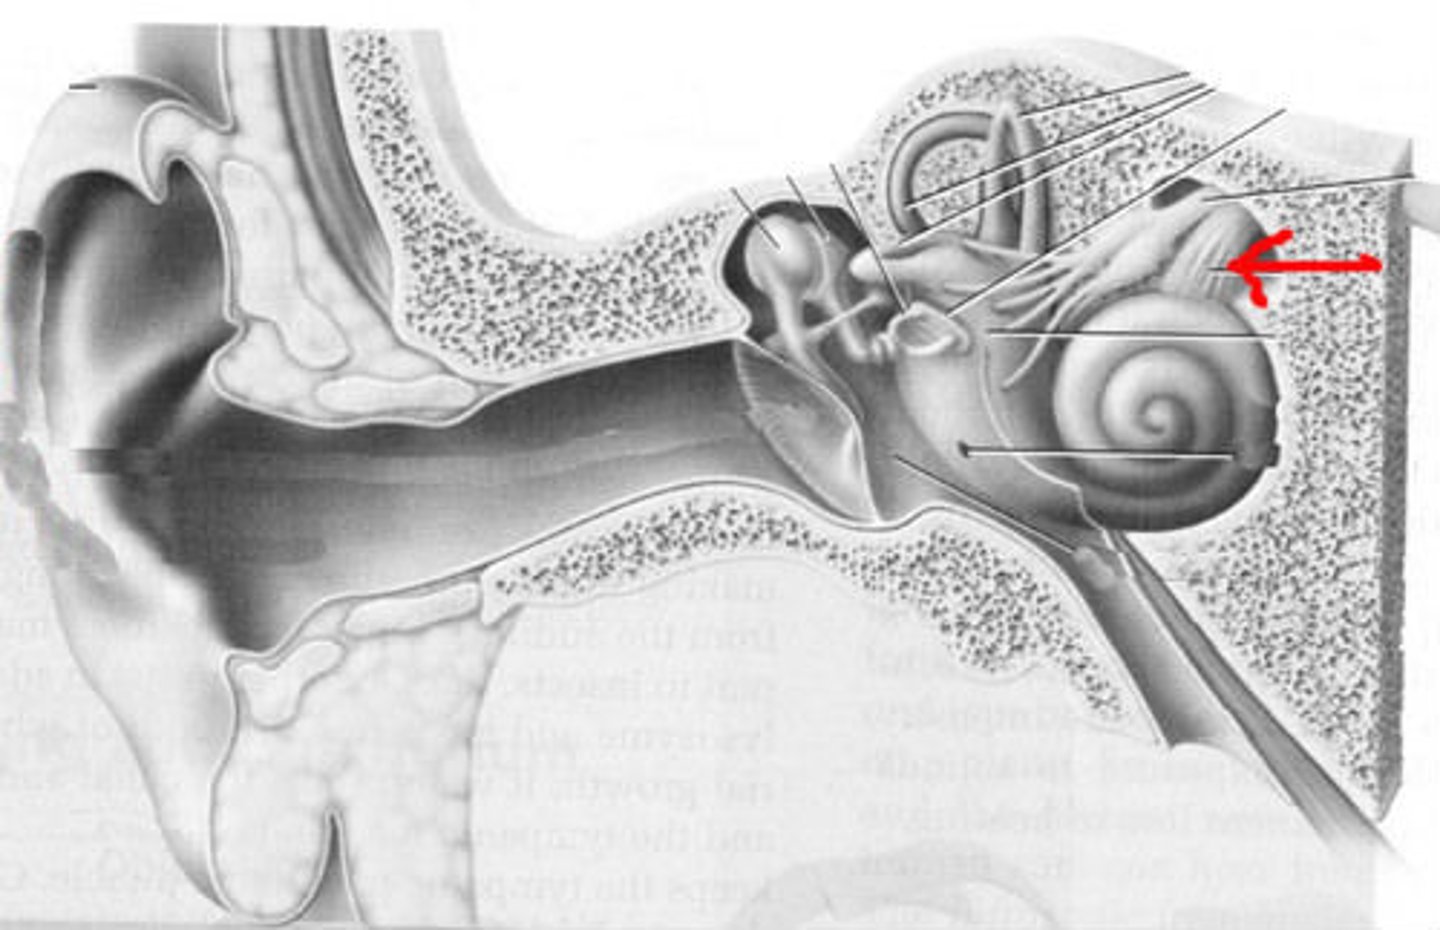

cochlea

cochlear nerve

labyrinth (osseous + membranous)

(general structure, ignore arrow)

oval window

round window

scala tympani

scala vestibuli

semicircular canals

spiral organ (of corti)

section of cochlea

stapes

vestibular nerve

vestibule

vestibulocochlear nerve